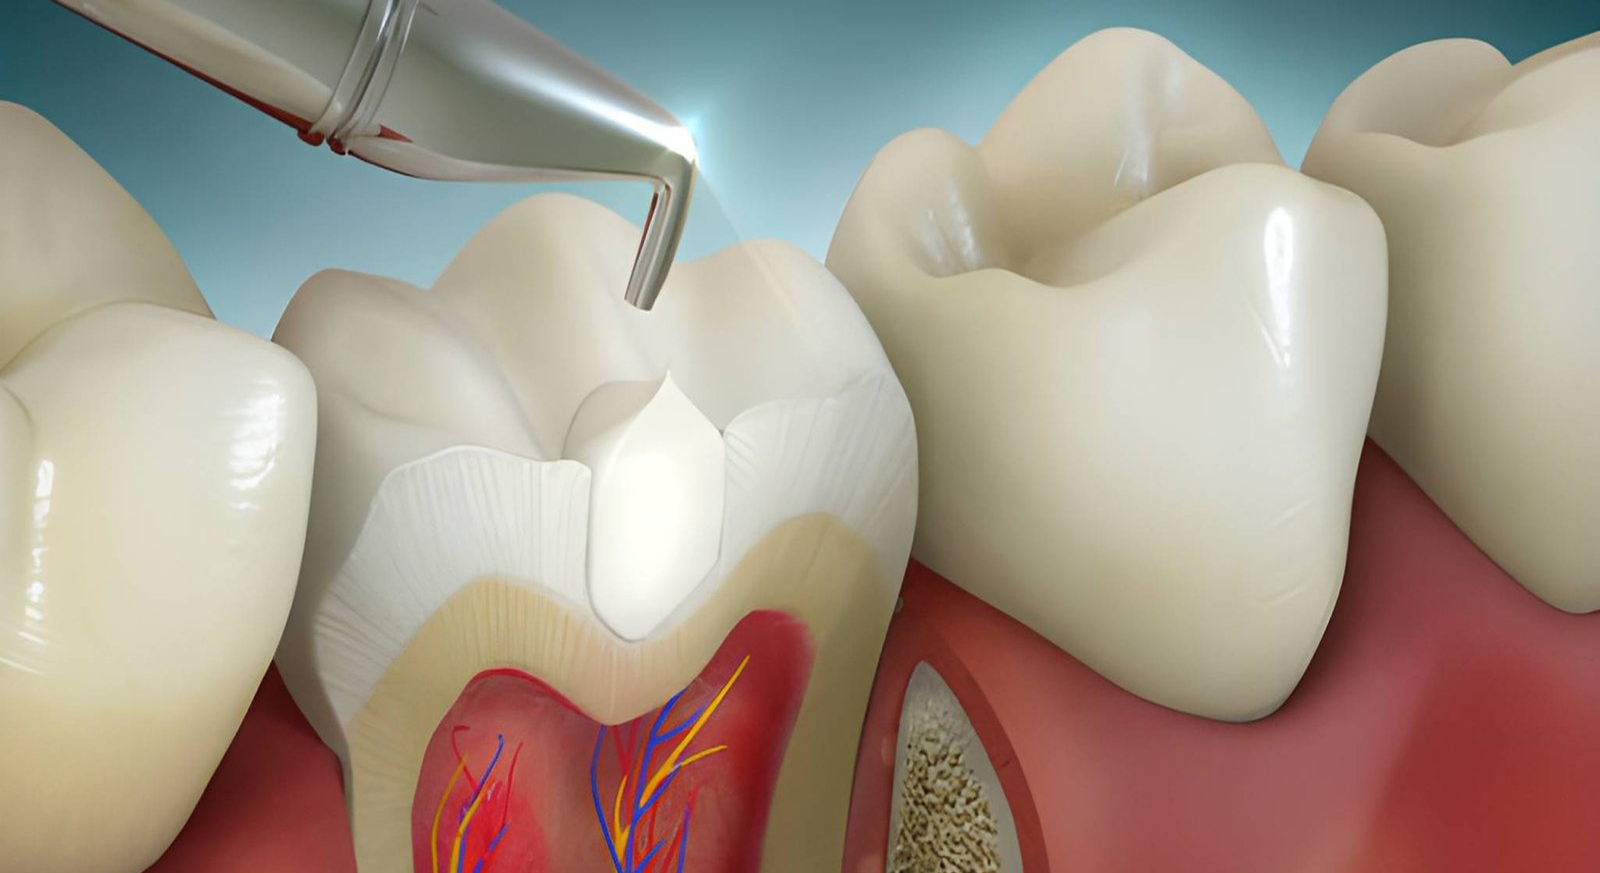

Composite Application

A high-quality composite resin is placed in layers, shaped to match the natural tooth structure, and hardened using a specialized dental light.

Filling & Finishing

The filling is polished and refined to blend naturally with surrounding teeth. Bite alignment is checked to ensure comfort and long-lasting performance.